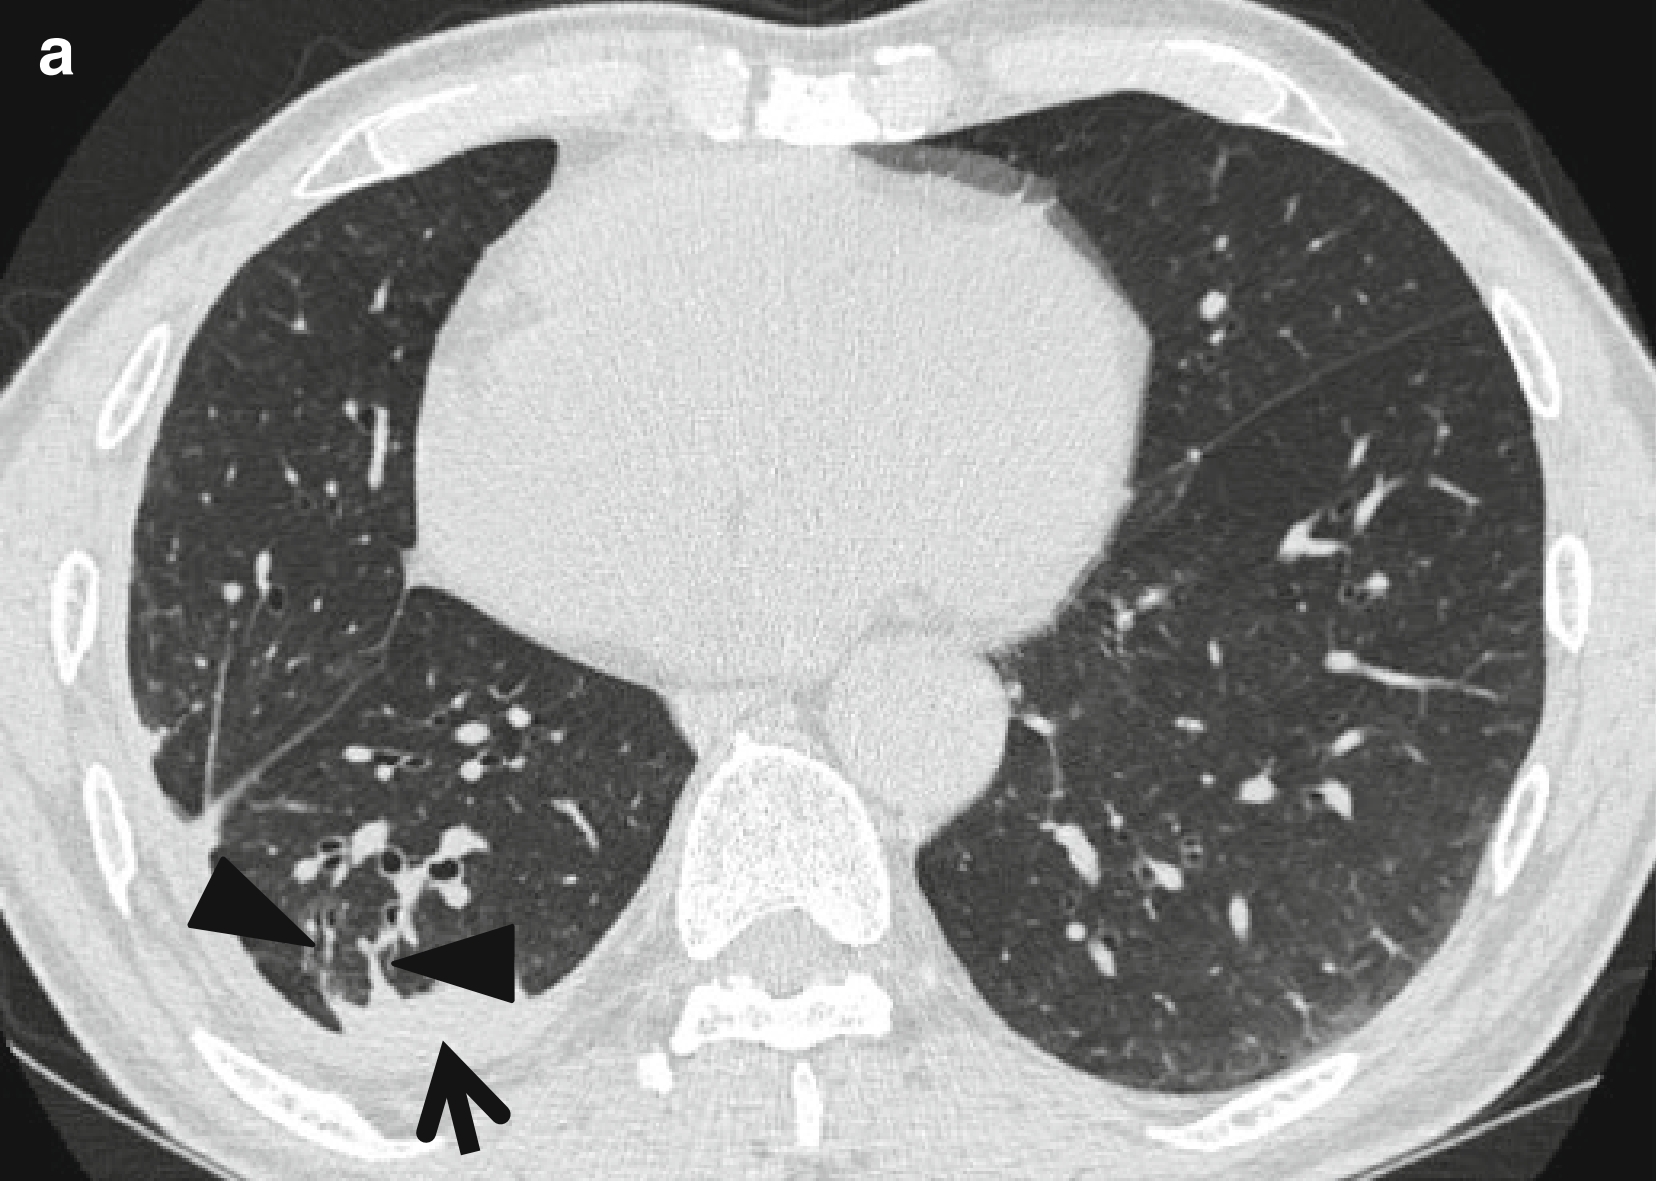

图1 圆形肺不张。

男,66岁,主诉气促和咳嗽。

(a,b)连续薄层 CT(层厚=1.5 mm)扫描于心室水平示右肺下叶(箭头所示)胸膜下圆形肺不张,并可见两条迁曲血管样的条索状软组织密度影(楔形箭头所示),由圆形肺不张的前缘延伸至肺门;这两种结构有助于理解降落伞征(参见彗尾征定义)。并且,可于不张肺组织的后方见胸腔积液和胸膜增厚,以及胸膜外肋骨下脂肪堆积。

(c)纵隔窗可见不张的肺组织强化(箭头所示)。